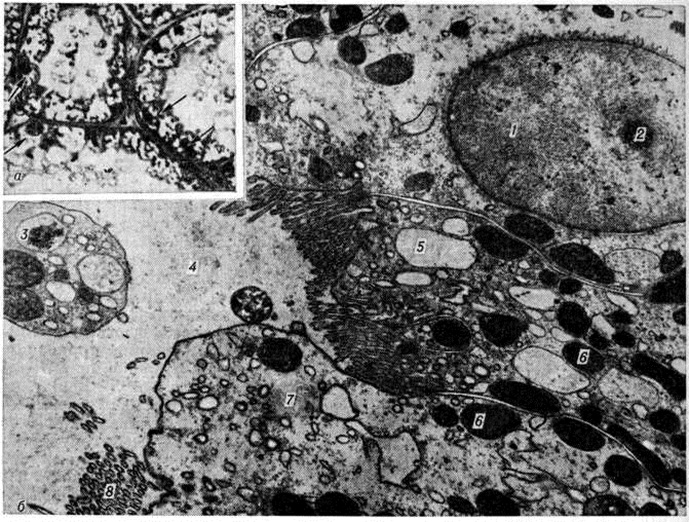

Патологическая анатомия. Морфологически изменения почек при острой Почечная недостаточность зависят от этиологии, периода болезни, своевременности, характера и объёма лечебный мероприятий. Макро и микроскопическая картина ишемических изменений почек, или так называемый шоковая почка (побледнение коркового вещества при полнокровии юкстамедуллярной зоны), чаще наблюдается при травматическом шоке, кровопотере и не характерна для процессов экзо и эндотоксического происхождения. При гистологический исследовании обнаруживают очаговые поражения эпителия канальцев с преобладанием гидропической дистрофии нефроцитов (рисунок 1). Электронно-микроскопическое исследование свидетельствует о выраженном и глубоком повреждении почечных канальцев: вакуолизации цитоплазмы вследствие расширения цистерн эндоплазматической сети; отёке или набухании митохондрий с появлением хлопьевидных уплотнений и фрагментацией крист; очаговой деструкции щёточной каёмки с парциальным отёком и секвестрацией апикальных отделов цитоплазмы. Реже развивается распространённый колликвационный некроз нефроцитов извитых почечных канальцев проксимальных и дистальных отделов нефрона. Все эти повреждения сопровождаются ферментными изменениями нефроцитов. Разрыв почечных канальцев (тубулорексис) считают типичным при шоке, хотя некоторые патологи считают это артефактом. При шоке, сопровождающемся гемолизом и миолизом, морфологический изменения в почках соответствуют гемоглобинурийному и миоглобинурийному нефрозу (смотри полный свод знаний: Миоглобинурия). После инфузионной терапии морфологический картина поражения почечных канальцев может изменяться: вследствие осмотического нефроза происходит вакуолизация, увеличиваются пиноцитозные пузырьки и наступает растяжение щёточной каёмки нефроцитов. В клубочках почечных телец отмечают малокровие, слущивание отдельных эндотелиоцитов с оголением базальных мембран, иногда субэндотелиальные отложения фибрина.

Тромбоз капилляров клубочков как проявление диссеминированного внутрисосудистого свёртывания крови наблюдается чаще при бактериемическом шоке и патологически протекающей беременности. К проявлениям диссеминированного внутрисосудистого свёртывания крови с развитием генерализованного феномена Швартцмана— Санарелли (смотри полный свод знаний: Швартцмана феномен) относят также симметричный кортикальный некроз почек (смотри полный свод знаний: Геморрагический кортикальный некроз почек). Различают тотальную, субтотальную, сегментарную и малую формы некроза. При тотальной форме сохраняются почечные пирамиды; при субтотальной — в корковом веществе встречаются островки непоражённой ткани; при сегментарной — очаги некроза имеют вид инфарктов, окружённых геморрагиями; малые формы удаётся выявить только при микроскопическом исследовании. При затянувшейся острой Почечная недостаточность некротизованное корковое вещество почки истончается. Отравление этиленгликолем влечёт за собой симметричный кортикальный некроз почек, сочетающийся с гликолевым нефрозом, а при патологии беременности — с острой гемоглобинурией, апоплексией и некрозом коркового вещества надпочечников, некрозом передней доли гипофиза. Гистологически отмечается коагуляционный некроз коркового вещества почки. В клубочковых кровеносных капиллярах и артериолах обнаруживают фибриновые тромбы (рисунок 2, а). Зона некроза ограничена демаркационным валом из полиморфно-ядерных лейкоцитов. Аргирофильный каркас разрушен. В дальнейшем некротизированные участки подвергаются организации, фиброзу и кальцинозу.

При гликолевом нефрозе почка увеличена, на разрезе влажная; гистологически определяется баллонная дистрофия эпителия канальцев проксимальных и дистальных отделов нефрона(рисунок 2, б) с кристаллами оксалатов в их просвете и внутри клеток. Электронно-микроскопическое исследование выявляет образование вакуолей в результате резкого расширения цистерн эндоплазматической сети. Нефроциты в состоянии баллонной дистрофии могут длительно не отторгаться, замедляя регенерацию ткани почки.

Острый гемоглобинурийный нефроз развивается при отравлении гемолитическими ядами (уксусной кислотой, мышьяковистым водородом, медным купоросом, аминосоединениями, нитросоединениями и другие). При этом морфологический изменения отражают транспорт гемоглобина по системе нефрона; для макроскопической картины типична черно-бурая радиальная исчерченность почечных пирамид, обусловленная наличием пигментных цилиндров (рисунок 3), дающих положительную реакцию Лепене (смотри полный свод знаний: Лепене способ) с бензидином. При отравлении уксусной кислотой гистологически обнаруживается поражение эпителия канальцев проксимальных отделов нефрона, обусловленное реабсорбцией гемоглобина, который выявляется в виде бензидин-положительных гранул в цитоплазме; при электронно-микроскопическом исследовании обнаруживается резорбция гемоглобина в вакуолях клеток с парциальным некрозом апикальных отделов, «перегруженных» пигментом, процесс сопровождается разрывом канальцев дистальных отделов нефрона с выходом в строму содержимого канальца, воспалительной реакцией вокруг него и последующей его облитерацией. Отравление гемолитическими ядами тиоловой группы (мышьяковистый водород, соединения меди и другие) проявляется острым гемоглобинурийным нефрозом в сочетании с коагуляционным некрозом нефроцитов.